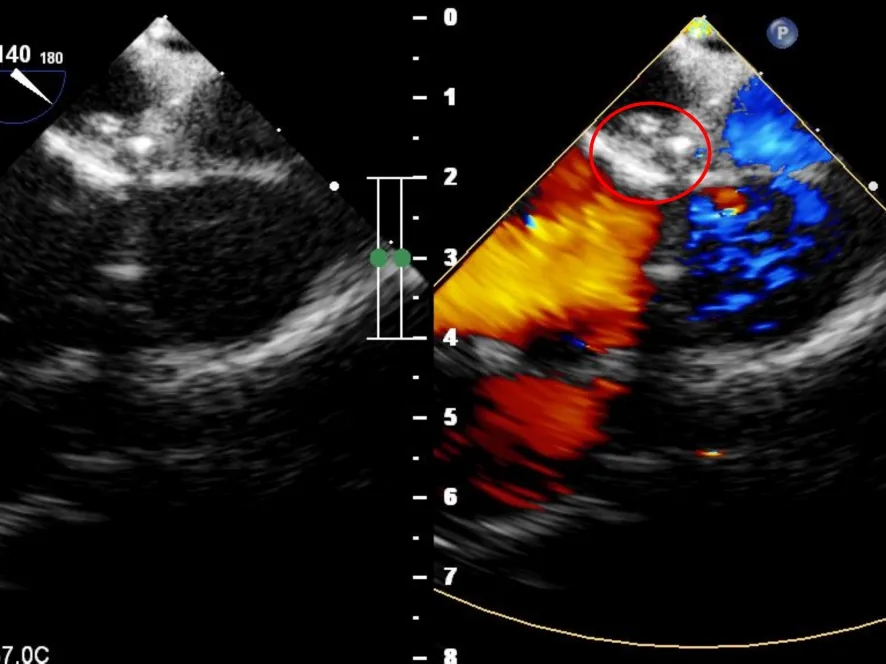

超声下可见左冠状动脉异常增宽

右心房后壁侧可见高速紊乱的血流信号

超声下可见封堵器形态位置正确,未见明显血流通过,封堵器盘面贴合,位置固定